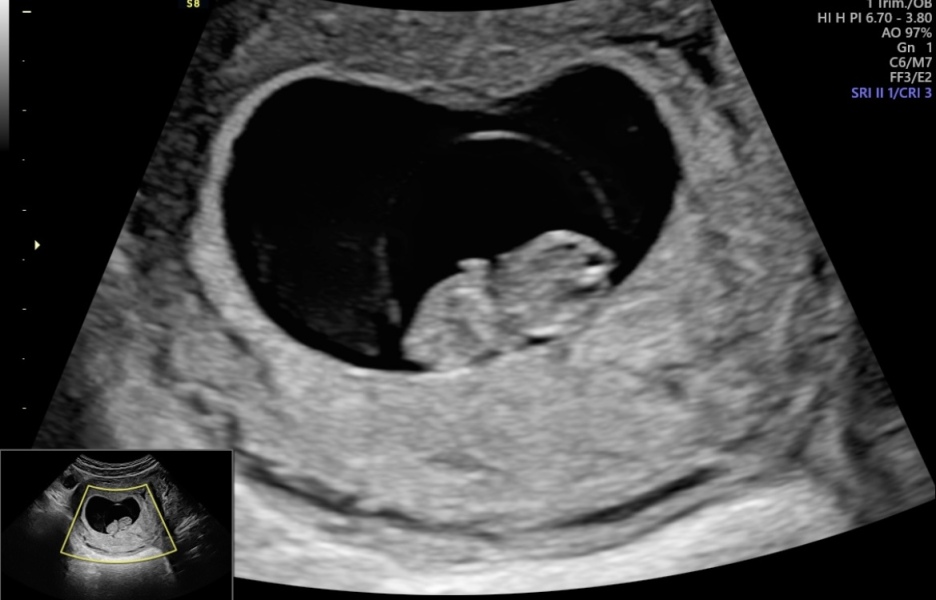

Went for a private scan this morning, twin has almost been fully reabsorbed and remaining baby has sped up some growing and is measuring 9 weeks exactly. Got to see it dancing around 💕 very relieved after some heavy bleeding this week!

MrsB2019x · 18/02/2024 15:02

Gorgeous scans ladies 😍😍😍

Oh all the scans are fab!! I also went for one on Saturday morning and baby measuring two days over so now 9+2 so feeling good and reassured 🥰

Amazing scans girls! I can’t believe we’re coming up to the 12 week mark already!